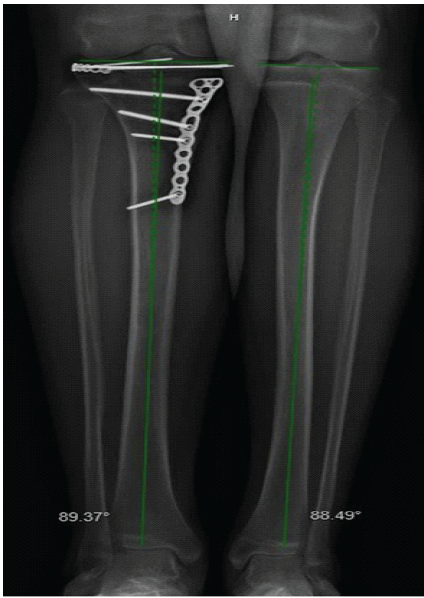

The patient was kept non-weight-bearing for 12 weeks postoperatively with instructions to work on knee range of motion. At 6 weeks post-operative, his range of motion was 15–90° and he was instructed to begin physical therapy. At 4 months post-operative, his range of motion was 5–120° and he was ambulating with a limp. At 7 months post-operative, both his range of motion and strength were full and symmetric to the contralateral side at 0–130°. He was asymptomatic and had returned to all desired activities, including gym class. X-rays demonstrated a healed fracture with well-maintained alignment and premature closure of the proximal tibial physis. There was no evidence of length-length or sagittal plane growth discrepancy (Fig. 4).

Figure 4: Lower extremity alignment films at 7 months post-operative demonstrating no significant asymmetry.